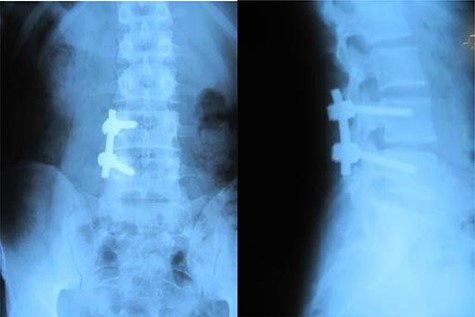

A 26-year-old male presented with pain over the lower lumbar area. Physical examination and laboratory tests were unremarkable with no neurologic deficit. X-ray and CT scans showed a lytic lesion with a sclerotic border in the right half of the body of the L5 vertebra (Figs 6 and 7). MRI showed a well-defined low signal lesion in T1 weighted images and high signal lesion in T2 weighted images (Fig. 8). The bone scan was negative. The patient underwent surgery and the lesion was extracted through the right pedicle and the remaining cavity was filled with an autologous bone graft from the iliac crest and right-side posterior fusion was done from L4 to L5 (Fig. 9). The pathology report was consistent with SBC. The patient had no recurrence seven years after surgery.

Case 2, Sagittal T2-weighted and T1-weighted MR images of lumbar vertebrae show the body and homogeneous cystic lesion of L5.